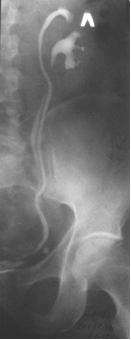

| Рис. 6.5. Прицельная рентгенограмма таза. Цистография. Определяется обширный дефект наполнения связанный со стенкой мочевого пузыря с неровными контурами. Рак мочевого пузыря. |